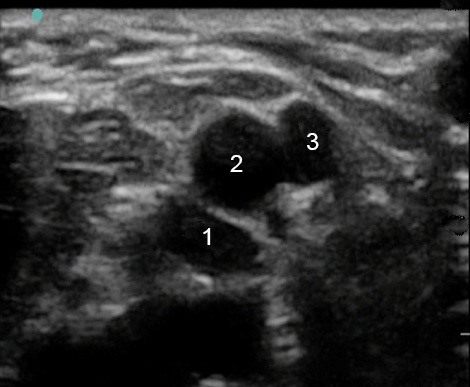

Peripheral IV (PIV) Brachial Vein Graphic and Image

Brachial Vein

Brachial Artery